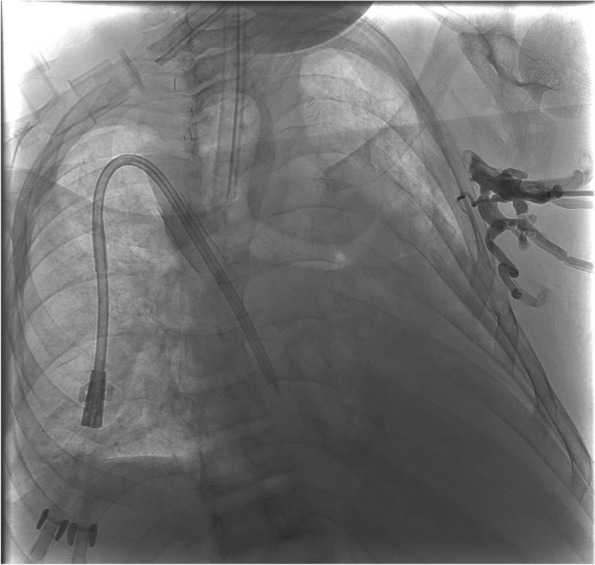

Axillo-caval extra-anatomic venous bypass creation via direct percutaneous puncture of the superior vena cava.

Abstract Image